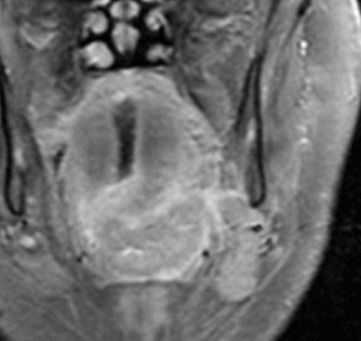

МРТ мягких тканей шеи с контрастированием. Распространения рака ротоглотки на парафарингеальное пространство.

МРТ мягких тканей шеи с контрастированием. Распространение рака ротоглотки на подчелюстное пространство.

МРТ мягких тканей шеи с контрастированием. Распространение опухоли корня языка на каротидное пространство.